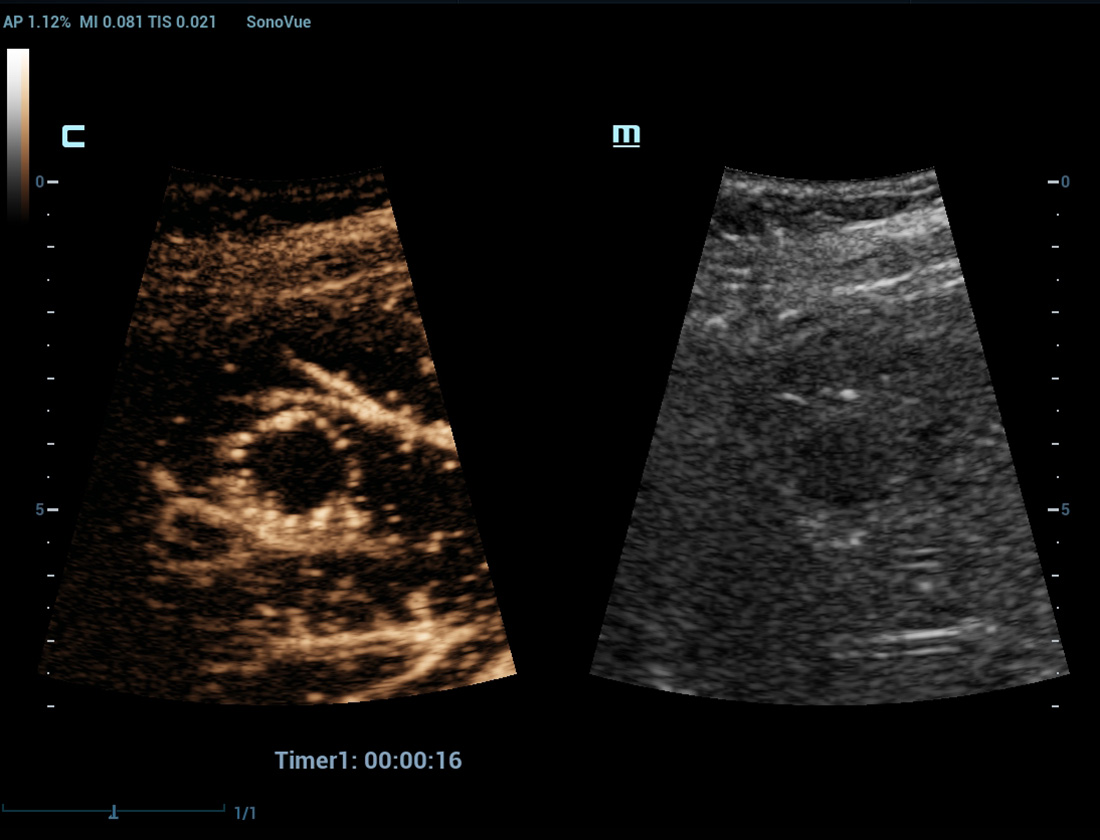

Geavanceerde CEUS

Geavanceerde CEUS

UWN+(Ultra-Wideband Niet-linear) CEUS

CEUS Borst kwaadaardig

Door gebruik te maken van zowel de 2e harmonische als niet-lineaire fundamentele signalen, maaktUWN+ een hoge gevoeligheid van bubbelsignalen en langere contrastperfusie met een lagere MI mogelijk, wat helpt bij tumorbeoordelingen.

UWN+-contrastbeeldvorming

Detecteer en gebruik zowel 2e harmonische als niet-lineaire fundamentele signalen voor het genereren van beelden met:

- Uitstekende agentgevoeligheid, zelfs bij een laag signaal

- Langere perfusietijd met lagere MI

- Betere visualisatie van perfusie van kleine bloedvaten met MFE (Micro Flow Enhancement)

Leverlaesies

Levermassa CEUS